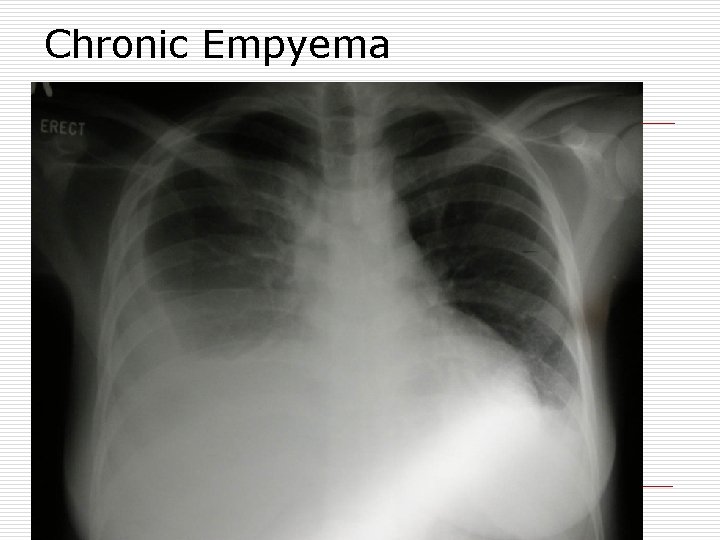

Diagnosis o X- ray chest: pleural effusion pyopneumothorax thickened pleura crowded ribs o CT chest: confirm diagnosis thickened pleura complications o Chest sonography: fluid collection loculations

Chronic Empyema